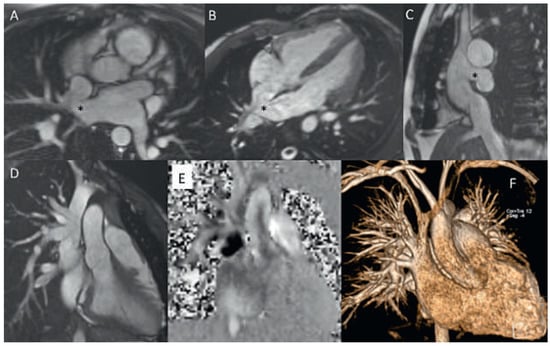

Figure 5.

Uncorrected sinus venosus defect from SVC-type with partial anomalous pulmonary venous drainage (PAPVD) of the right upper pulmonary vein. SSFP cine still frames in axial, oblique and sagittal orientation (A−C), SVC with PAPVD in SSFP cine still frame (D), PC CMR orthogonal en face view of the defect and L−R shunt (black area) (E), CE MRA angiography with visualisation of the the PAPVD (F). * Sinus venosus defect.